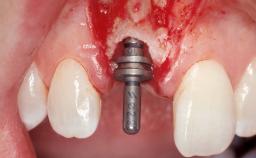

Late Placement of an Implant in a Maxillary Left Central Incisor Site

A 36-year-old female patient was referred for the replacement of the upper left central incisor (tooth 21), which had fractured. Although the tooth had been asymptomatic for many years, the crown began to loosen, at which time she presented to her dentist for an assessment. Teeth 21 and 22 had both been endodontically treated many years previously. She was a healthy individual and a non-smoker.

Type of Implants Two-Piece

Bone Augmentation Horizontal|Staged

Augmentation Materials Xenogenous|Membrane

Bone Volume Deficient horizontally, requiring prior grafting